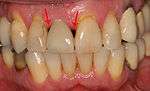

Soft tissue (gingiva) reconstruction

The gingiva surrounding a tooth has a 2–3 mm band of bright pink, very strong attached mucosa, then a darker, larger area of unattached mucosa that folds into the cheeks. When replacing a tooth with an implant, a band of strong, attached gingiva is needed to keep the implant healthy in the long-term. This is especially important with implants because the blood supply is more precarious in the gingiva surrounding an implant, and is theoretically more susceptible to injury because of a longer attachment to the implant than on a tooth (a longer biologic width).[28](pp629–633)

When an adequate band of attached tissue is absent, it can be recreated with a soft tissue graft. There are four methods that can be used to transplant soft tissue. A roll of tissue adjacent to an implant (referred to as a palatal roll) can be moved towards the lip (buccal), gingiva from the palate can be transplanted, deeper connective tissue from the palate can be tranplanted or, when a larger piece of tissue is needed, a finger of tissue based on a blood vessel in the palate (called a vascularized interpositional periosteal-connective tissue (VIP-CT) flap) can be repositioned to the area.[25](pp113–188)

Additionally, for an implant to look esthetic, a band of full, plump gingiva is needed to fill in the space on either side of implant. The most common soft tissue complication is called a black-triangle, where the papilla (the small triangular piece of tissue between two teeth) shrinks back and leaves a triangular void between the implant and the adjacent teeth. Dentists can only expect 2–4 mm of papilla height over the underlying bone. A black triangle can be expected if the distance between where the teeth touch and bone is any greater.[18](pp81–84)

From these theoretical risks, derive the real world complications. Long-term failures are due to either loss of bone around the tooth and/or gingiva due to peri-implantitis or a mechanical failure of the implant. Because there is no dental enamel on an implant, it does not fail due to cavities like natural teeth. While large-scale, long-term studies are scarce, several systematic reviews estimate the long-term (five to ten years) survival of dental implants at 93–98 percent depending on their clinical use.[1][2][3] During initial development of implant retained teeth, all crowns were attached to the teeth with screws, but more recent advancements have allowed placement of crowns on the abutments with dental cement (akin to placing a crown on a tooth). This has created the potential for cement, that escapes from under the crown during cementation to get caught in the gingiva and create a peri-implantitis (see picture below). While the complication can occur, there does not appear to be any additional peri-implantitis in cement-retained crowns compared to screw-retained crowns overall.[40] In compound implants (two stage implants), between the actual implant and the superstructure (abutment) are gaps and cavities into which bacteria can penetrate from the oral cavity. Later these bacteria will return into the adjacent tissue and can cause periimplantitis. As prophylaxis these implant interior spaces should be sealed.[41]